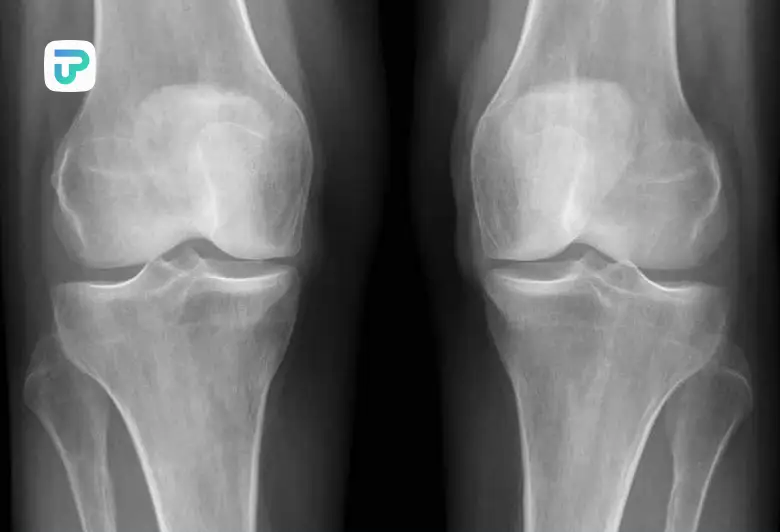

۴. نقرس و آرتروز زانو

آرتروز زانو نیز بهدلیل تخریب تدریجی غضروف، میتواند درد را به نواحی پایینتر منتقل کند.

در این موارد، داروهای ضد التهاب غیراستروئیدی (NSAIDs) مثل ایبوپروفن یا ناپروکسن تحت نظر پزشک تجویز میشود.